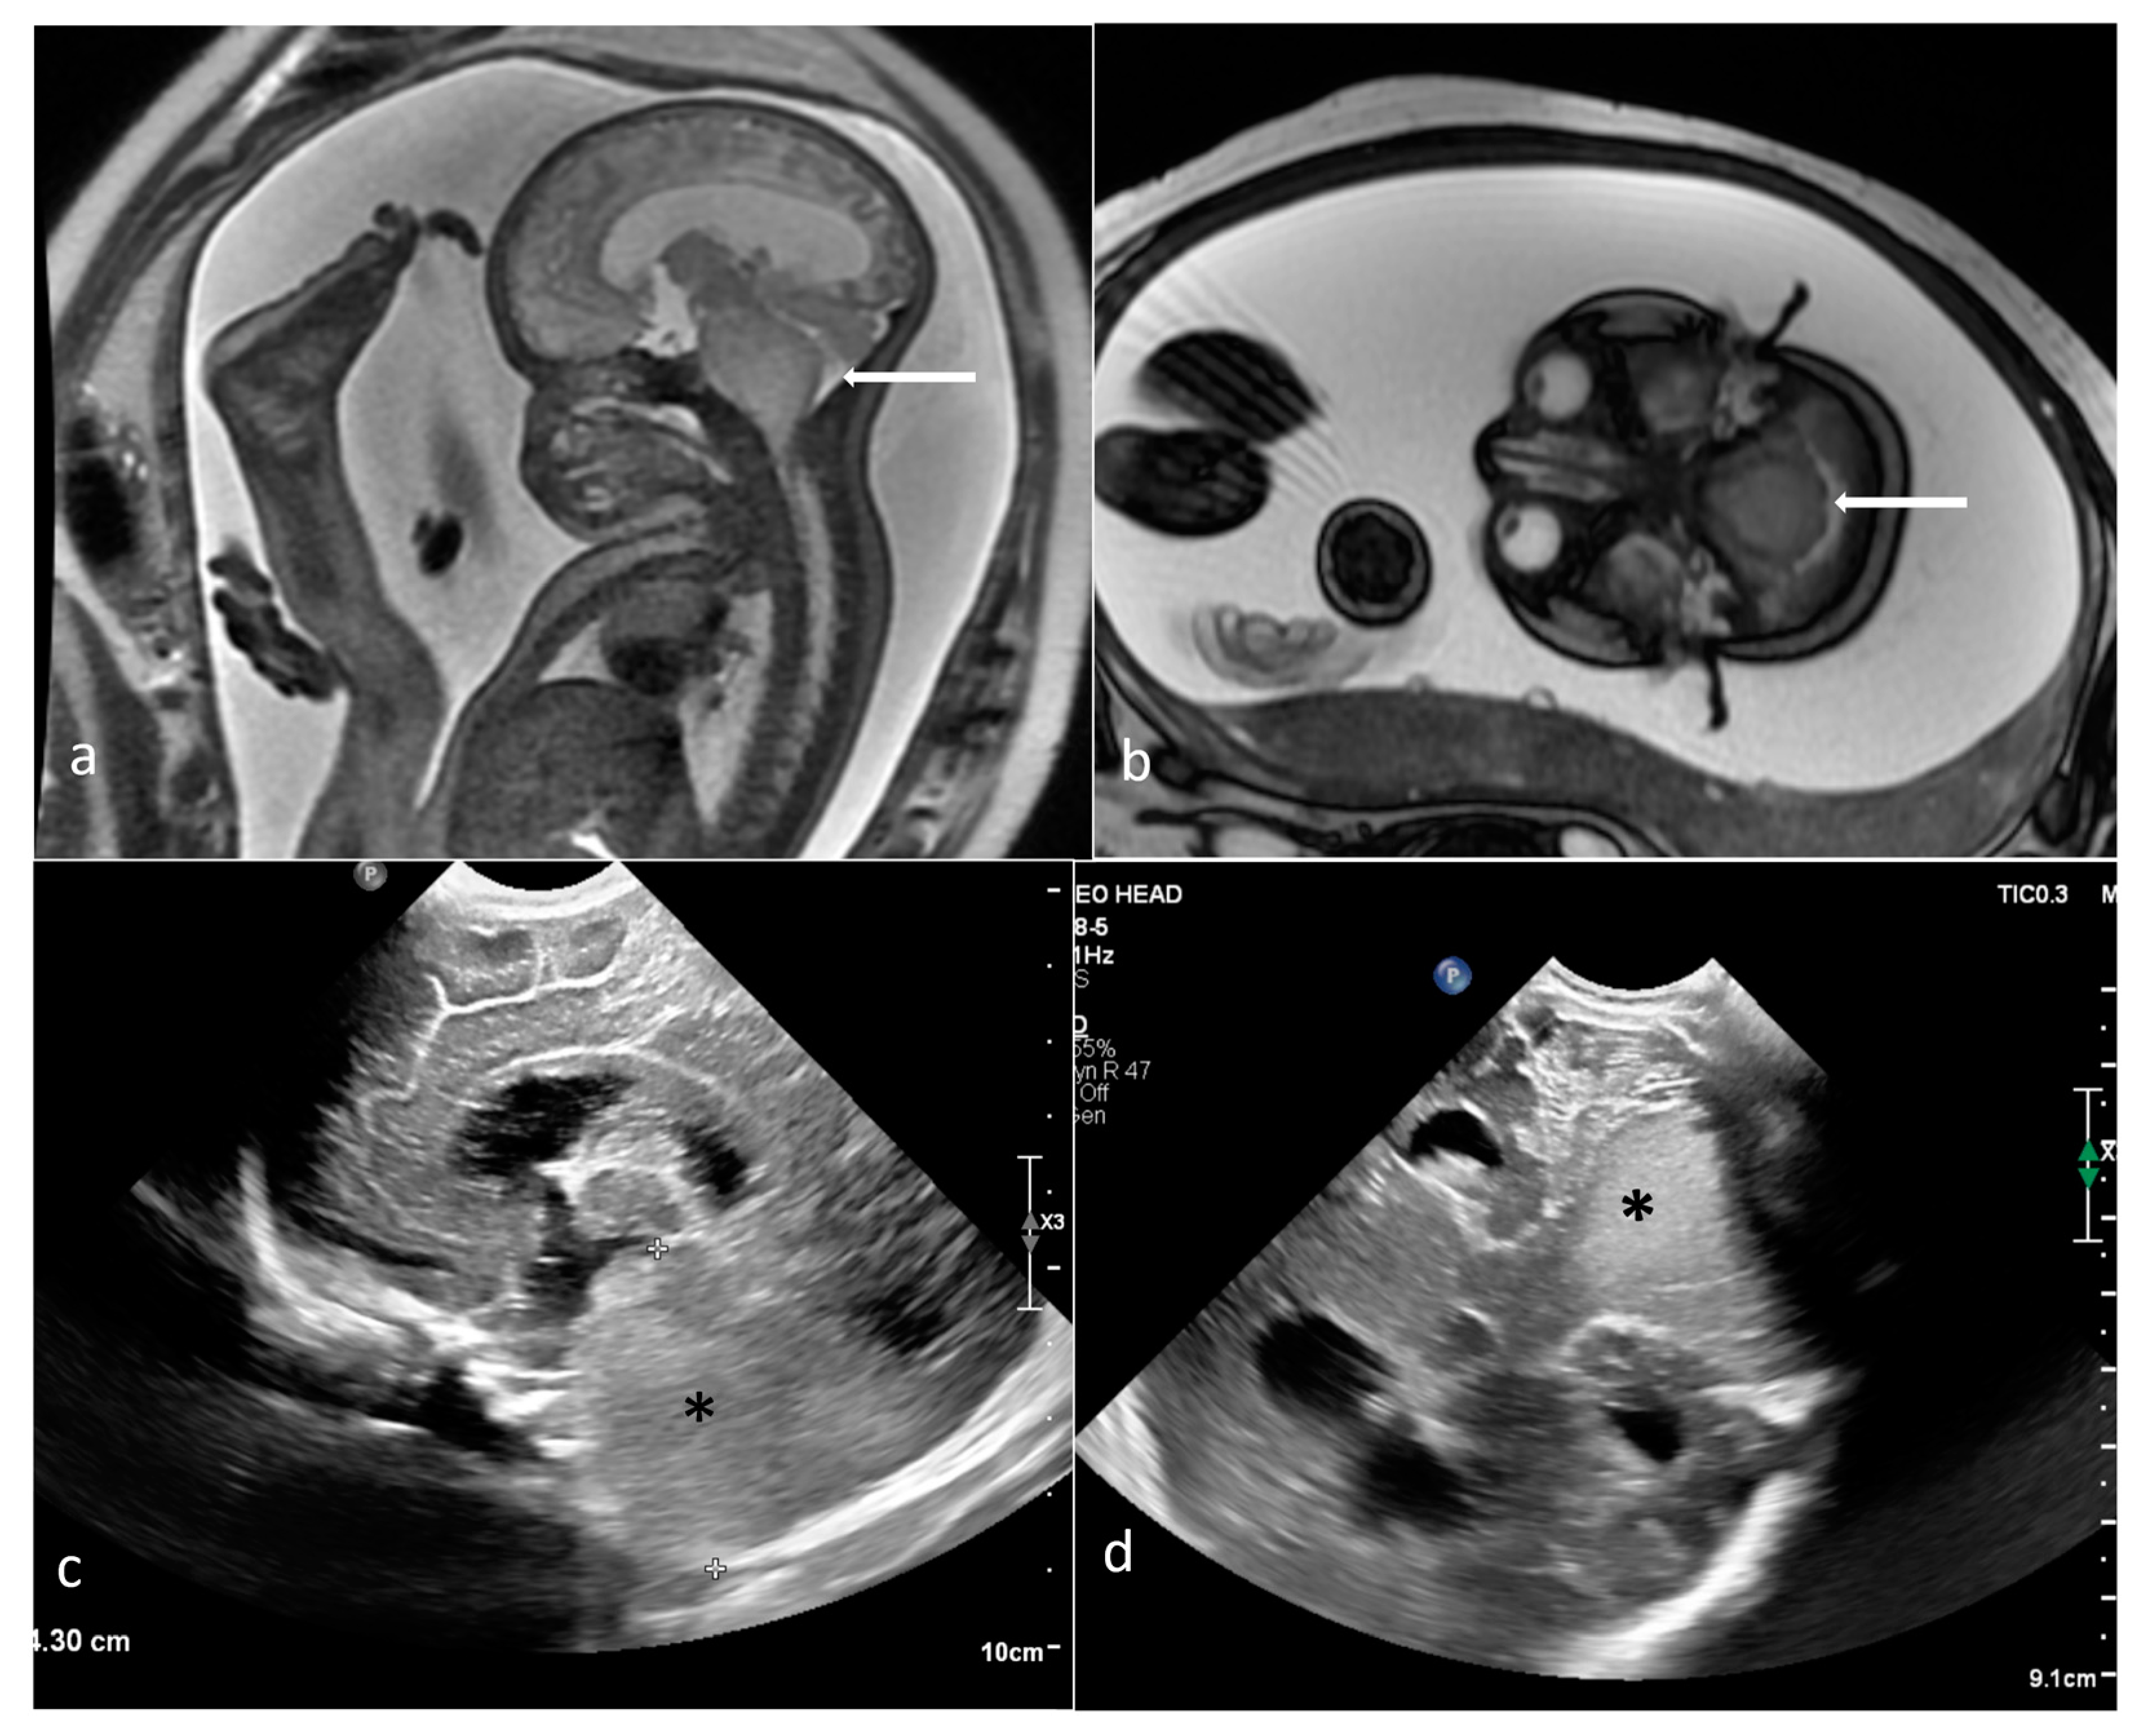

| Teratoma | sacrococcygeal | 25 | 268 [2.5–1145.165] | yes (13/17) [918–1661) | cystic (6) mixed (19) | yes 8/13 | yes (3/4) |

| head and neck | 13 | 176.1 [1.78–877.11] | yes (9/13) (796–1294) | solid (3) mixed (8) cystic (2) | yes (8/13) | yes (1) | |

| thorax and abdomen | 8 | 32 [1.49–134.98] | yes (3/6) | mixed (3) solid (3) cystic (2) | yes (4/5) | yes (1) | |